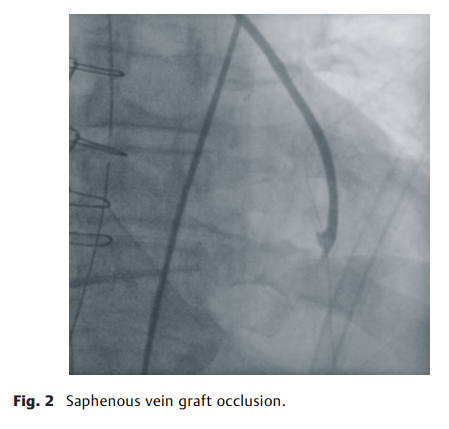

ICA 对3例患者(17%)的临床或手术决策有影响。在一名患者中,左胸内动脉 (LITA)的远端狭窄,因此进行双重抗血小板治疗6个月【图1】,两名 (11%) 患者进行了旁路移植物修复和额外的旁路移植术,这是由于一名患者的隐静脉移植物到钝缘支2阻塞【图2】,另一名患者有明显的 T 型移植物狭窄和移植物到左前降支阻塞【图3】。LITA。在这3例患者中,相应的外科医生认为ICA都优于TTFM。【图4】展示了令人满意的T型移植物血管造影。

图2. 隐静脉移植物闭塞。